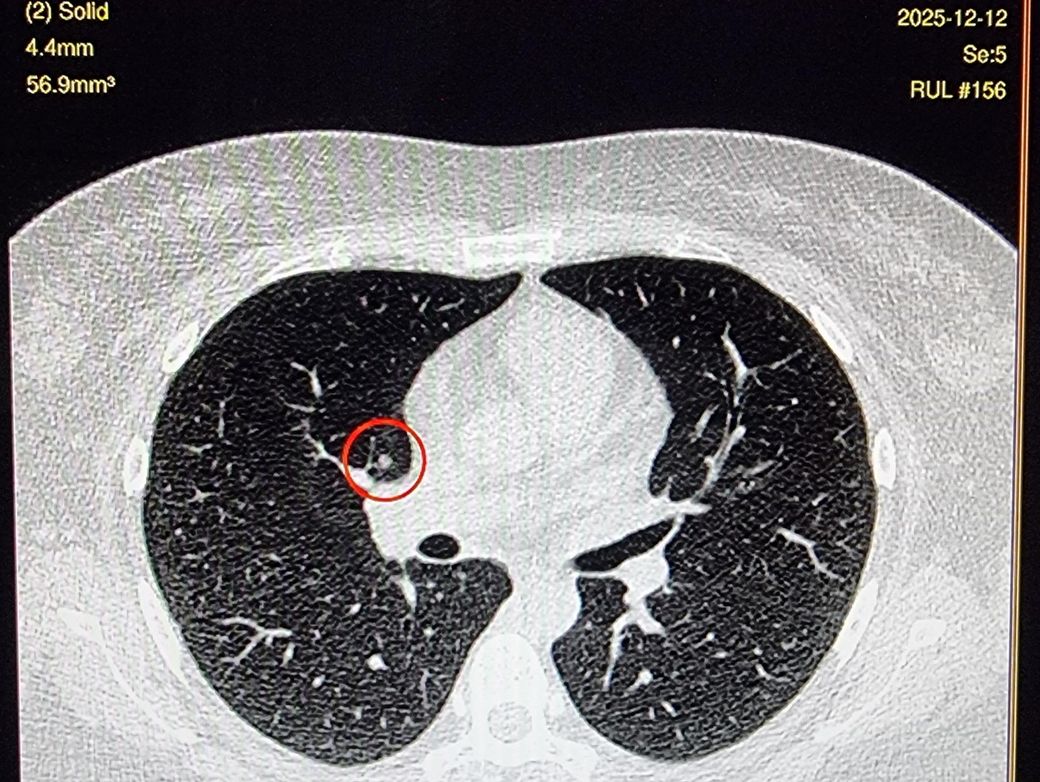

*좀더 하얀색인 사진 2장은 24년 조영제 폐CT 이고, 나머지 3장은 25년 저선량 CT사진입니다.

25년에 같은 저선량 CT에서 lucas라는 AI가 찾아낸 사진 2장은 빨간동그라미로 되어있습니다.*

♧ 고형 같나요 간유리 같나요?

Ai 는 우상엽 solid라는데 오늘 2차병원에서 중간위치고 간유리에 가깝다라고 들어서요

solid nodule인지 ground glass nodule인지는 clear cut하게 나누어지는 것이 아닙니다. 결절이 색이 또렷하면 solid nodule인 것이고 흐지부지하면 ground glass nodule인 것입니다. 이건 육안 소견을 두고 말하는 것입니다. 따라서 일부 nodule에 있어서는 판독하는 의사에 따라 소견이 다를 수 있습니다.